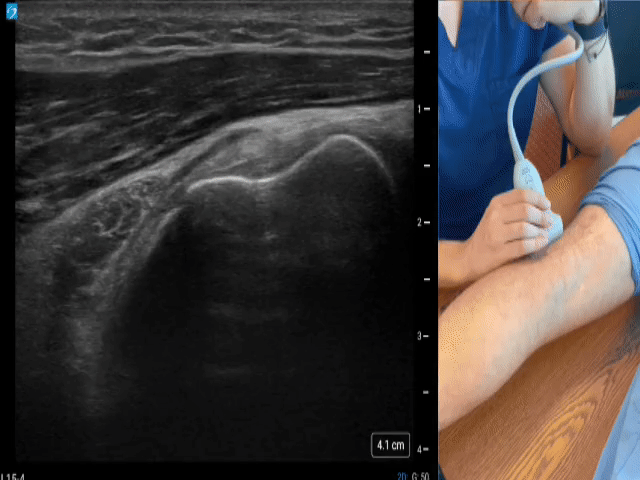

Knee Gallery - Suprapatellar/quad tendon (Short axis)

Position: Knee extended, partially bent. Location: Place the transducer transverse over the superior patella region. Once the quadriceps tendon is identified, scan proximally to evaluate the rectus femoris. Note the vastus medialis (medial) and vastus lateralis (lateral) as they come into view proximally.